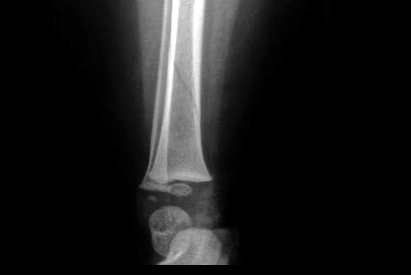

A toddler’s fracture is a minor break or fracture of the shin bone (tibia), often referred to as a ‘hair-line fracture’. This type of injury is typically caused by a simple fall or twisting of the leg and is very common in children under 3 years of age. Your child may well have started limping, or refused to walk or stand on their leg for no apparent reason; you may not even remember them falling or injuring themselves.

Your child may have an x-ray. The nurse practitioner or doctor will make this decision based on the history of the injury, their examination and the age of your child. Toddler’s fractures don’t always show up on the first x-ray because they are so small; we sometimes ask you to bring your child back to one of our clinics after 7 to10 days and we may repeat the x-ray at this stage.